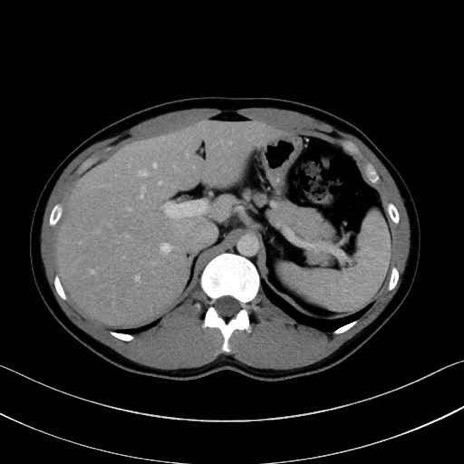

腰方形筋(quadratus lumborum muscle)のCT画像の解剖

腰方形筋 (Quadratus lumborum)